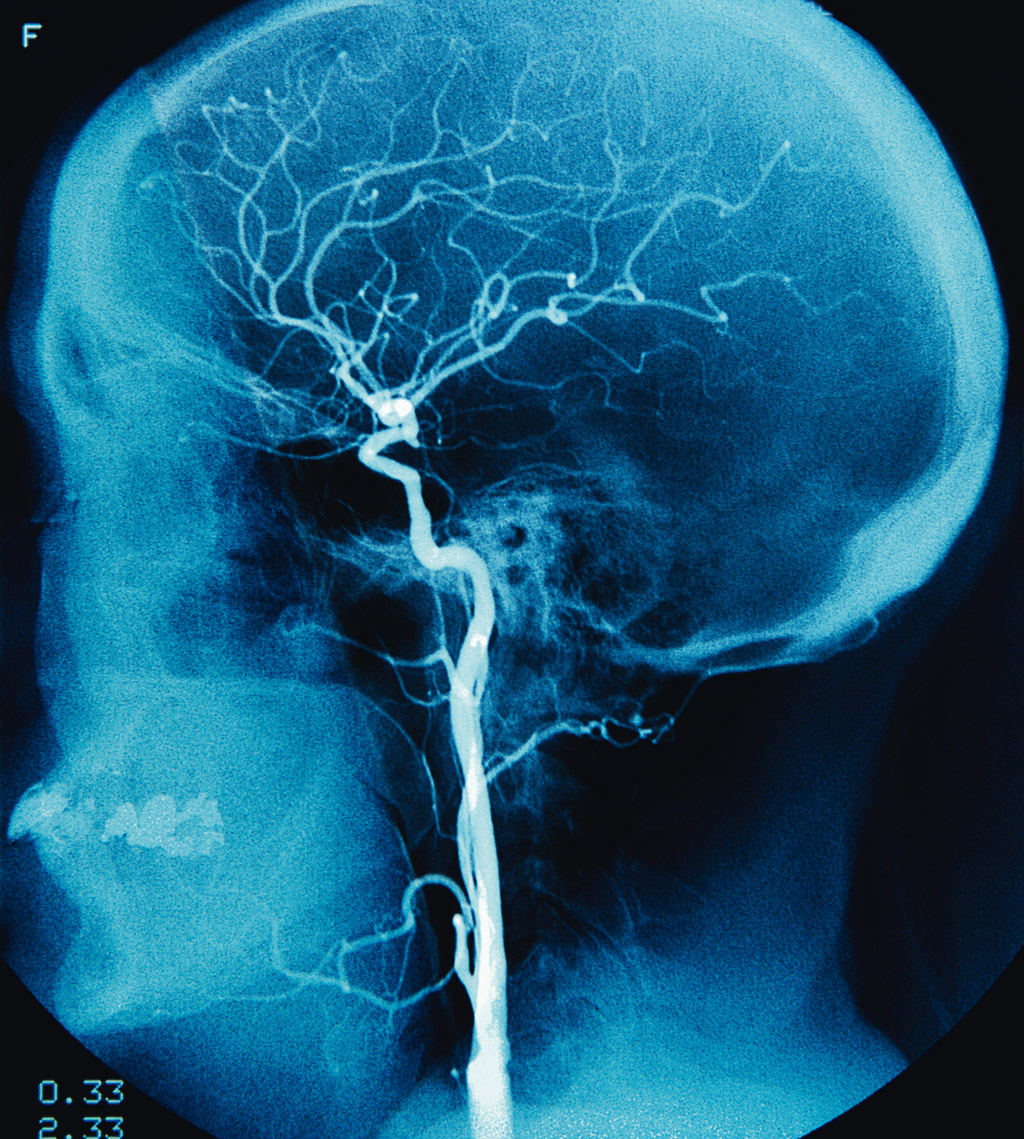

Pokaźnych rozmiarów mózg człowieka to niewątpliwie jedna z wielu dziwacznych cech i ewolucyjnych zagadek gatunku. Pokaźnych rozmiarów mózg człowieka to niewątpliwie jedna z wielu dziwacznych cech i ewolucyjnych zagadek gatunku. Robert Llewellyn / Corbis